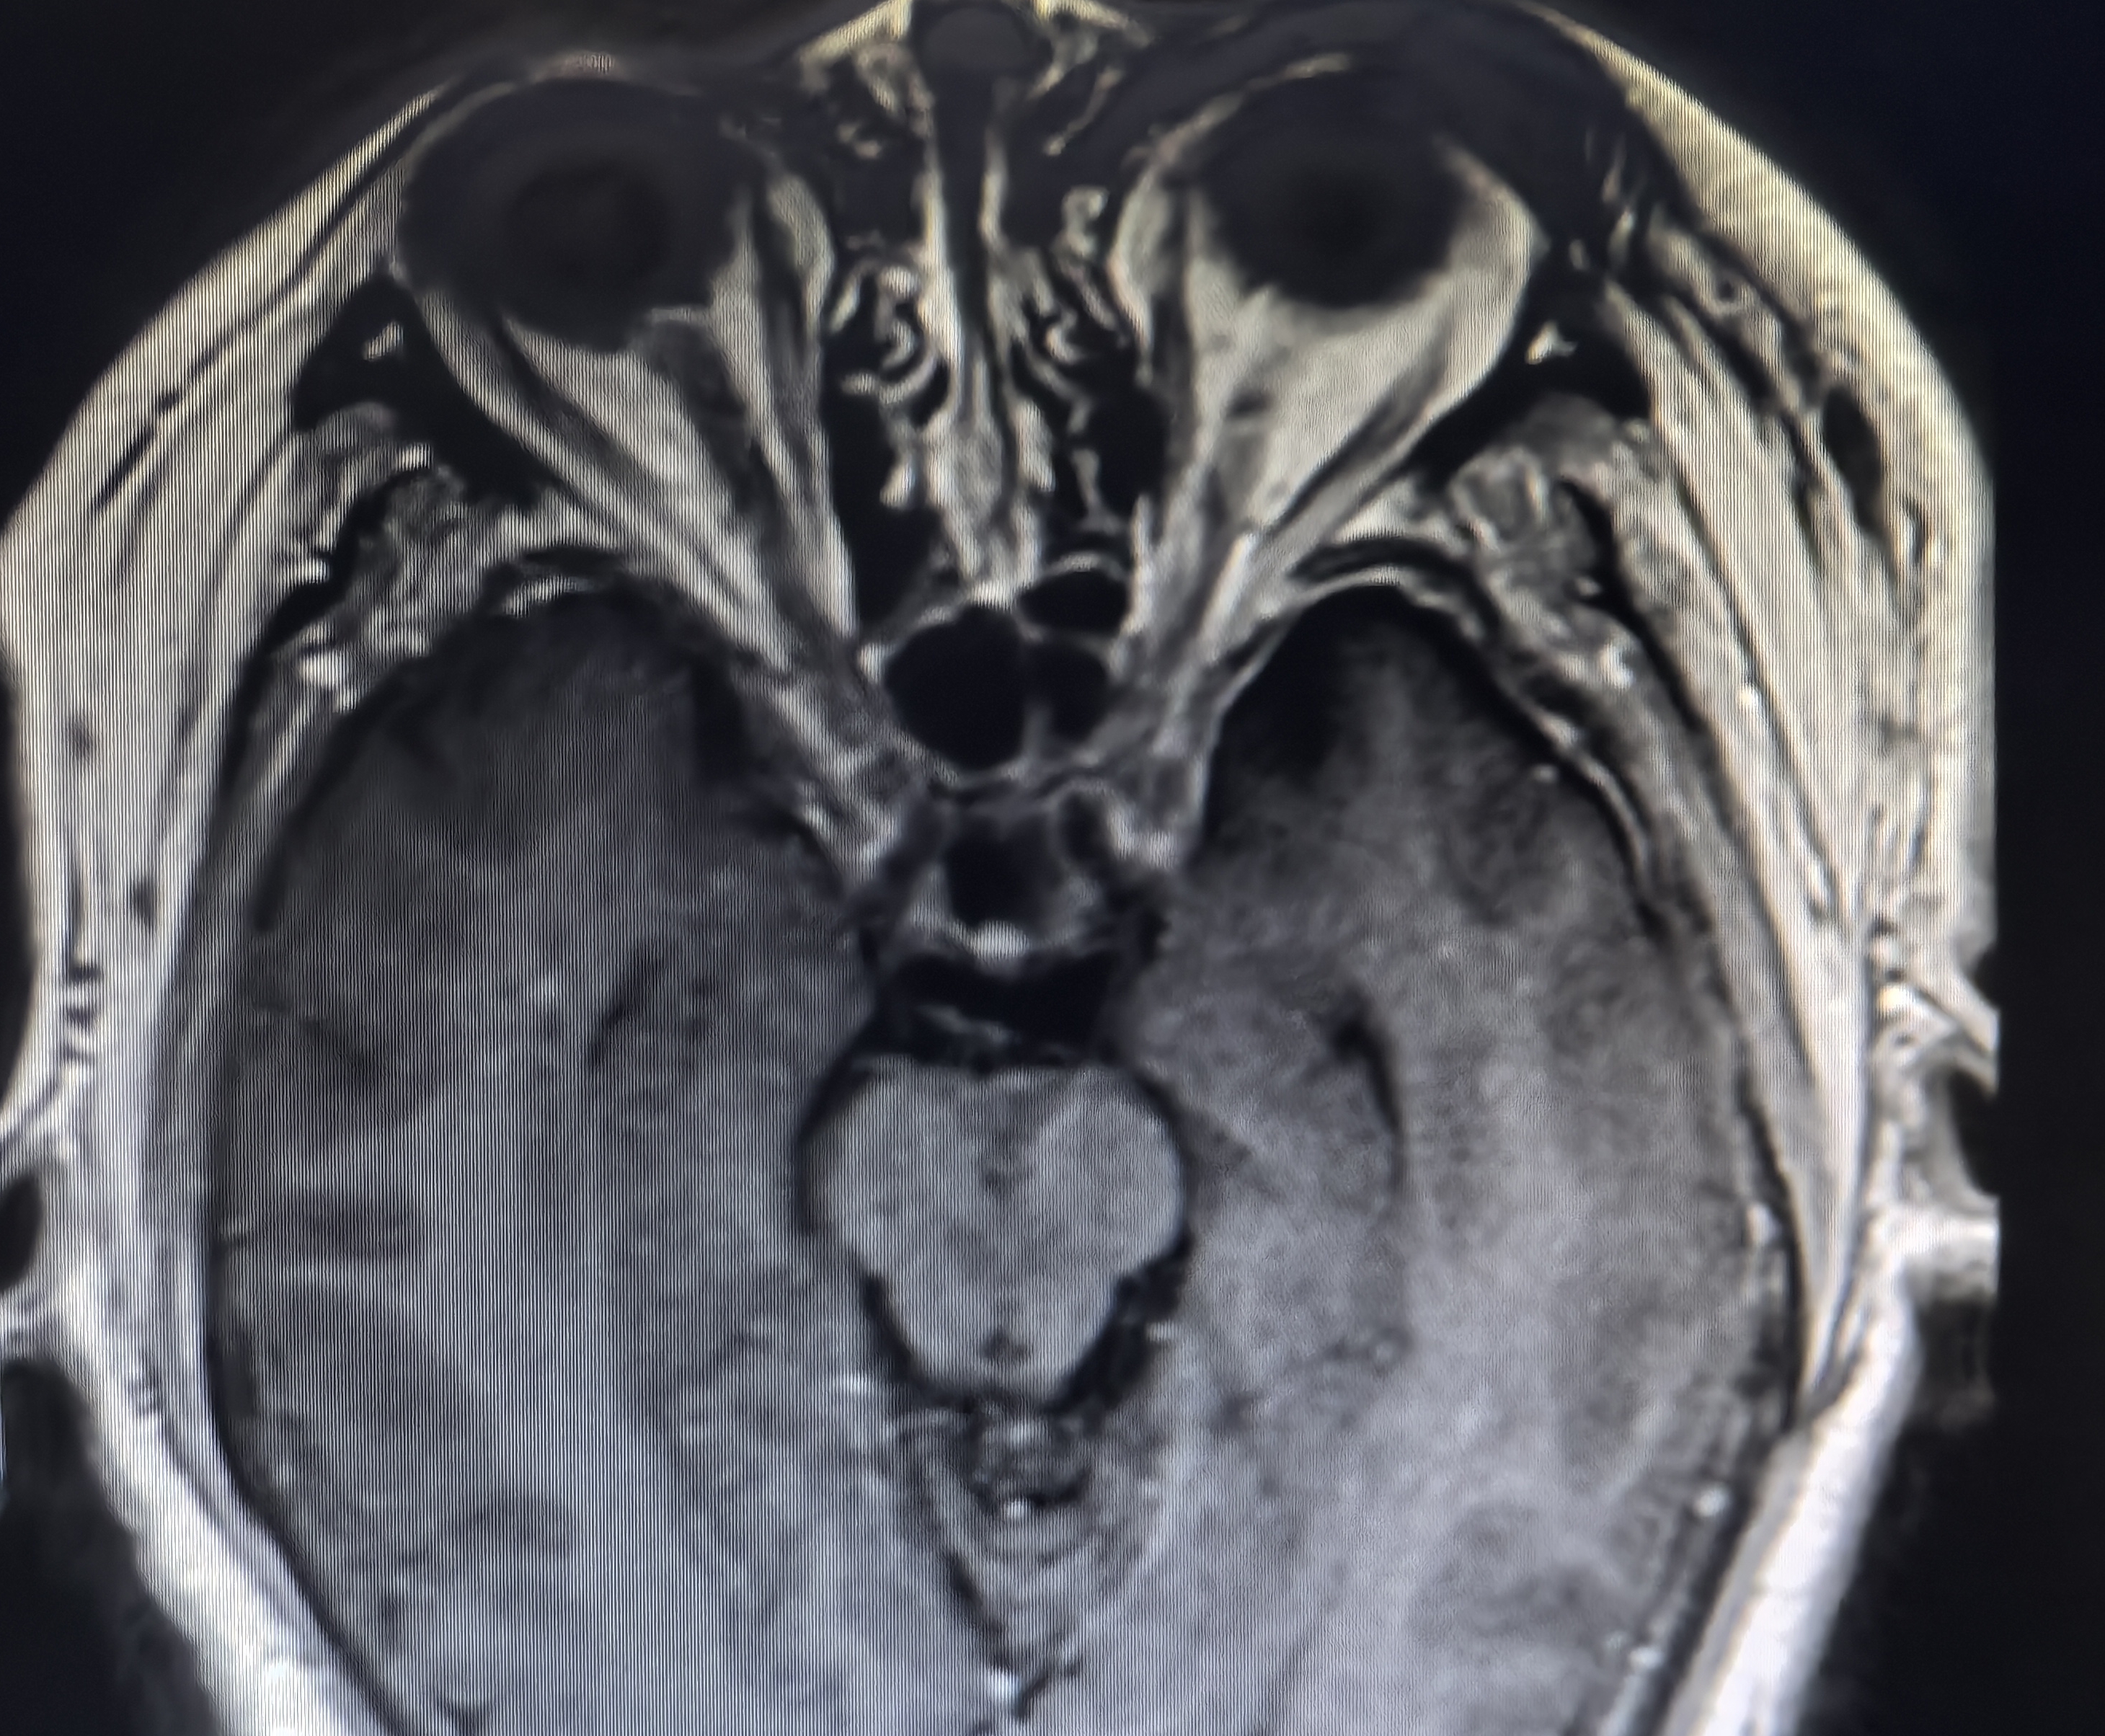

下面展示本病房几例病例:

肿瘤不大,重在规范。

病例一